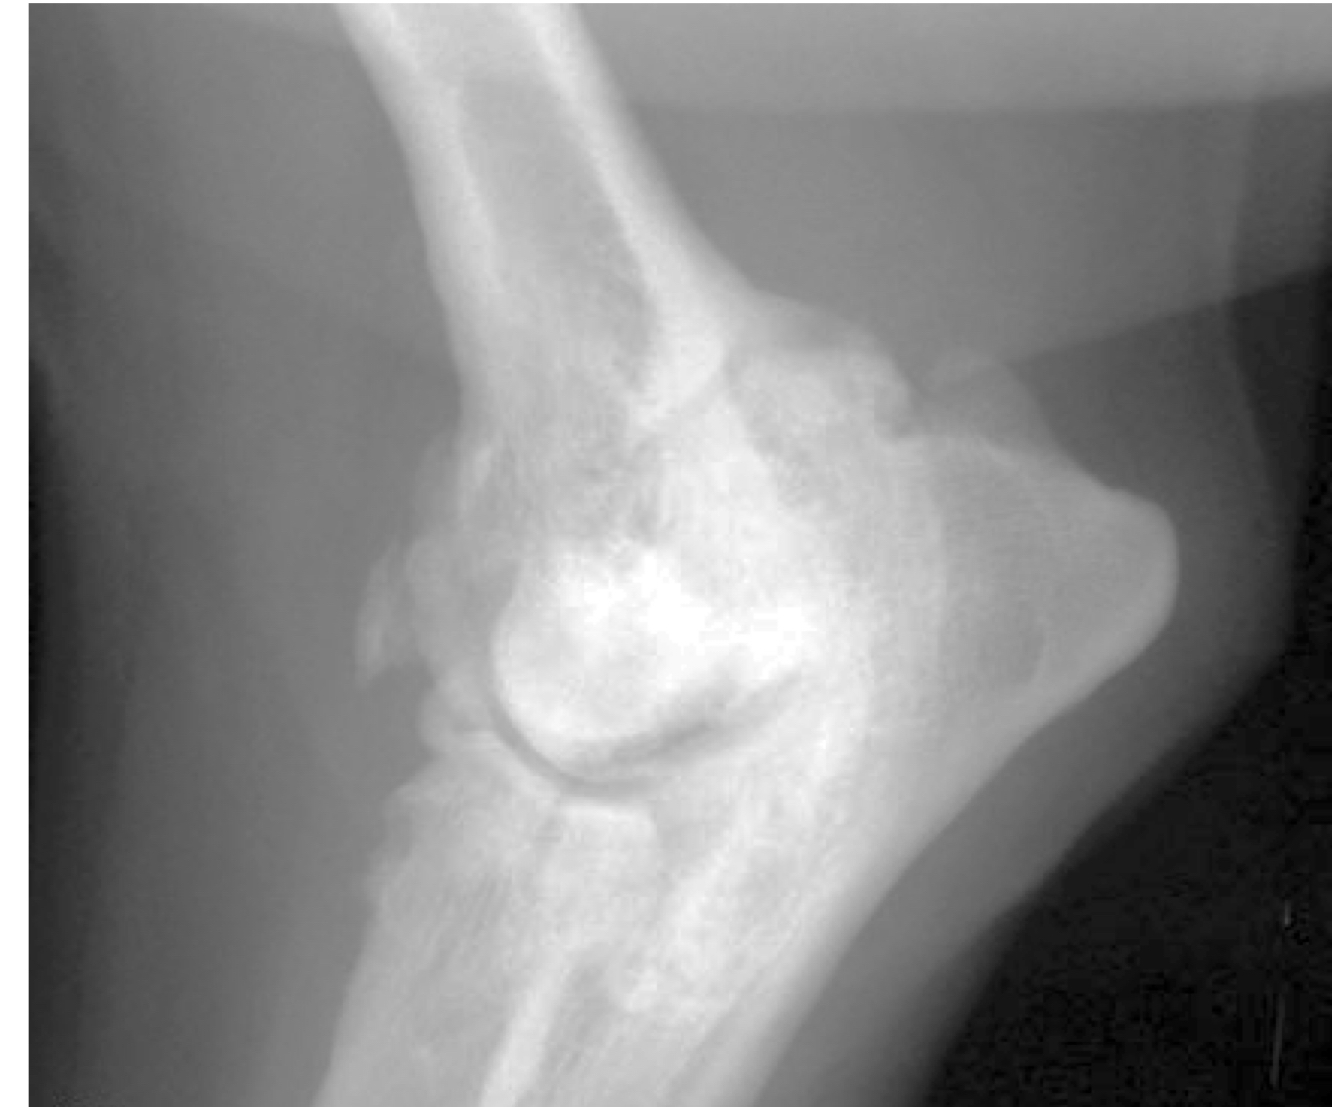

What wrong

lytic lesions in carpus